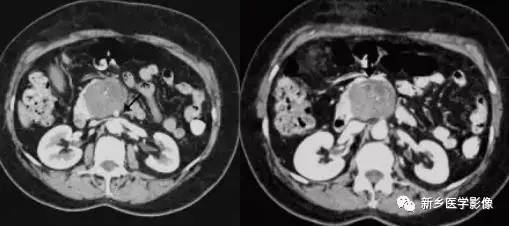

随着医学技术的不断进步,新型诊断技术如超声内镜、计算机断层扫描(CT)、磁共振成像(MRI)等已被广泛应用于胰腺肿瘤的诊断,这些技术的运用大大提高了早期胰腺癌的检出率,为患者的治疗赢得了宝贵的时间。